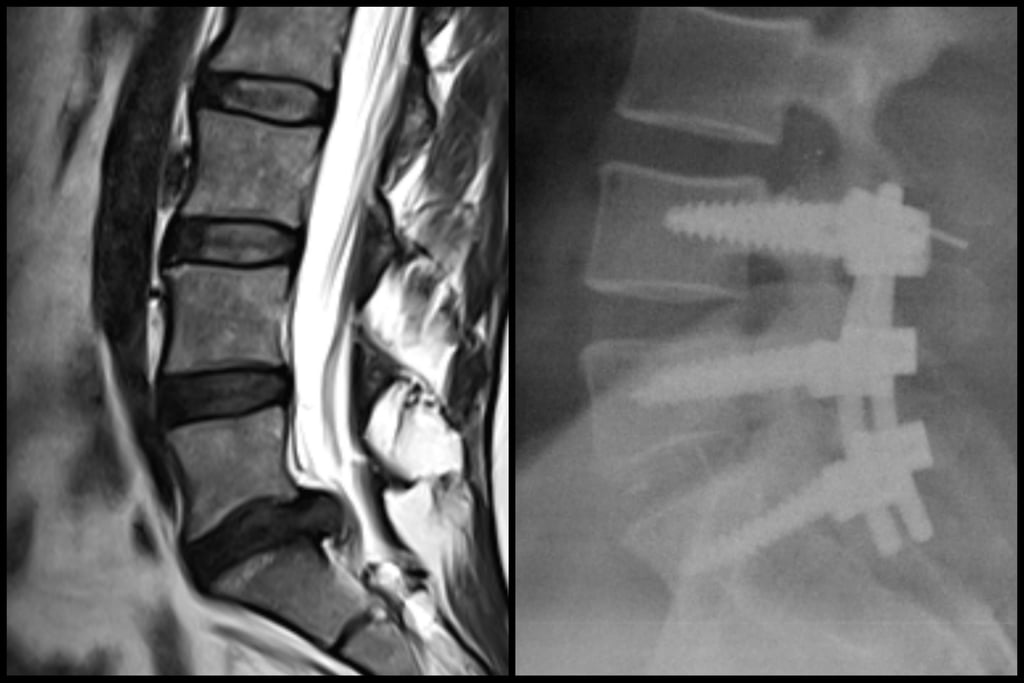

Artrodesis instrumentada, disectomia, cifoplastia, vertebroplastia, descompresion medular, liberacion radicular.